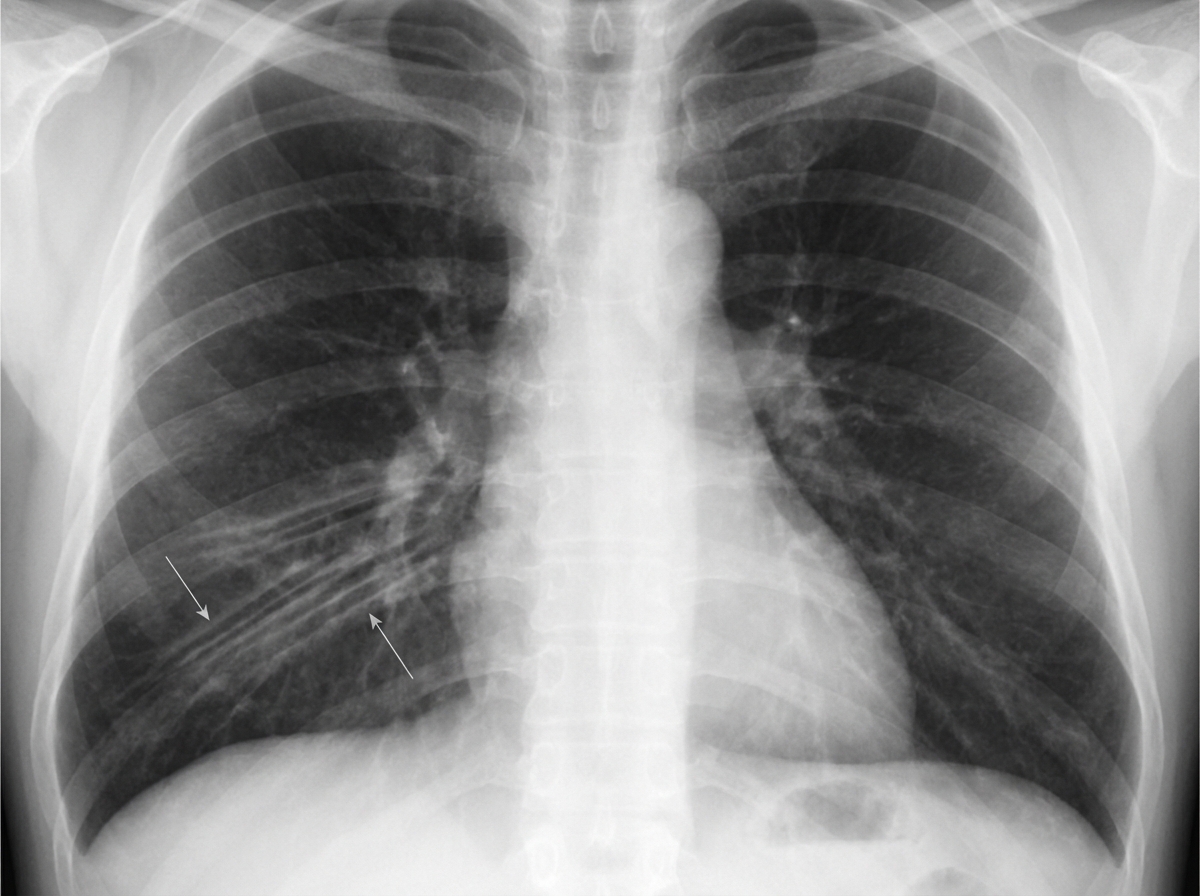

A 65-year-old man is brought to the emergency department after coughing up copious amounts of blood-tinged sputum at his nursing home. He recently had an upper respiratory tract infection that was treated with antibiotics. He has a long-standing history of productive cough that has worsened since he had a stroke 3 years ago. He smoked a pack of cigarettes daily for 40 years until the stroke, after which he quit. The patient appears distressed and short of breath. His temperature is 38°C (100.4°F), pulse is 92/min, and blood pressure is 145/85 mm Hg. Pulse oximetry on room air shows an oxygen saturation of 92%. Physical examination shows digital clubbing and cyanosis of the lips. Coarse crackles are heard in the thorax. An x-ray of the chest shows increased translucency and tram-track opacities in the right lower lung field. Which of the following is the most likely diagnosis?